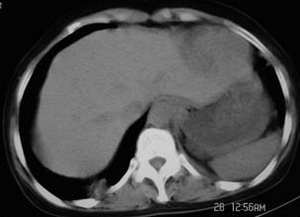

左侧胸廓容积缩小,纵隔左移,左下肺支气管闭塞.考虑中心型肺癌并左肺下叶不张,建议纤支镜.

左侧肺部体积缩小,纵隔向患侧偏移,左下肺支气管阻塞,中央型肺癌合并肺不张可能性大。

考虑中心型肺癌并左肺下叶不张